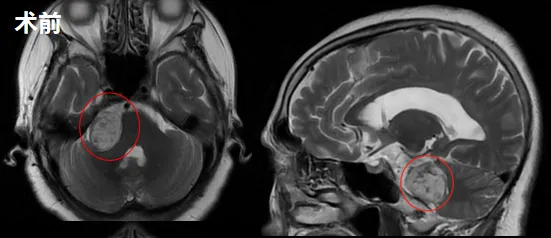

家属遂带其至当地医院就诊,经2021年5月及10月两次MRI检查,最终确诊为右侧听神经瘤(体积20mm×15mm×19mm),并发脑积水。

正当家属权衡治疗方案时,2022年10月复查显示肿瘤已增大至32mm×22mm×26mm,超过3厘米临界值,手术切除成为必要选择。